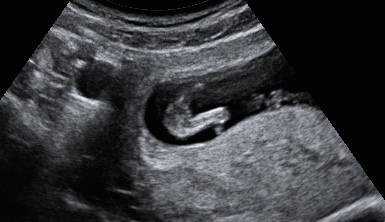

12 weeks 4 days

I know potty shots at this gestation are not that reliable,but just putting this up for a bit of fun to pass the time. I don't have a pic of the nub unfortunately.Attachment 22557Attachment 22557

Looks like a little girl.

Looks girly

I think there are times that you can tell early on. Sometimes it's obvious,others it's not. It's all for fun in the end and interesting to see how many were right or wrong